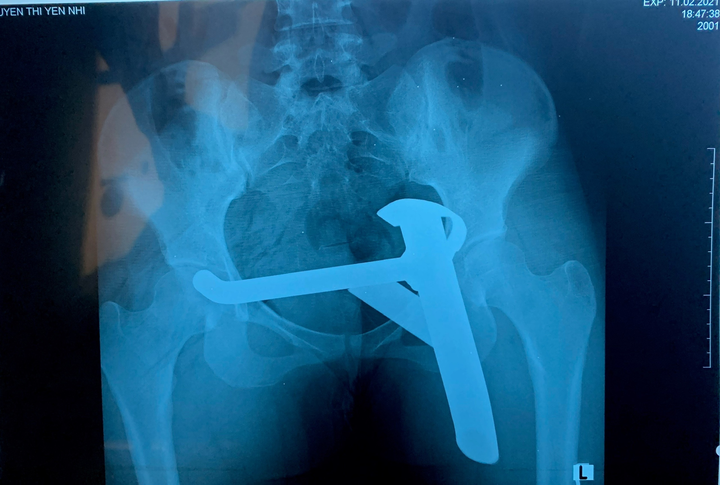

Các bác sĩ xác định thanh kim loại đâm sâu vào vùng mông, sát phần hậu môn nguy cơ tổn thương thần kinh ngồi. Bệnh nhân được chỉ định chụp X-quang khung chậu rồi đưa đến phòng phẩu thuật.

Ảnh chụp X-Quang.